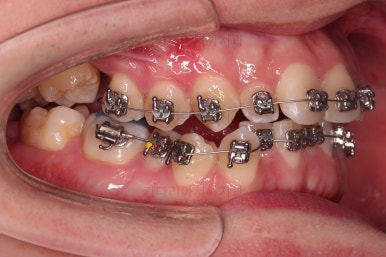

미니스크류가 식립되었고요.

결손치아도 오른쪽, 부정교합도 오른쪽이어서 오른쪽 위아래 각 1개씩 식립이 되었어요.

물론 윗니는 앞으로 당기는 용도, 아랫니는 뒤로 미는 용도였습니다.